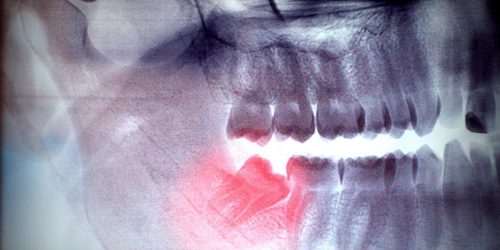

wisdom teeth - My Gentle Dentist

Wisdom Teeth

Wisdom teeth usually erupt in the late teens and are frequently a source of pain at the back of jaws/back teeth.

Mostly, these teeth don’t have any space in the jaws to erupt in proper positions and may require extractions.

My Gentle Dentist Arana Hills will see you ASAP if you have any wisdom tooth related problem.

We are highly trained in dealing with the extraction of these teeth, whether it be surgical or simple.